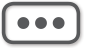

图3-1-2-5 导水管支架植入